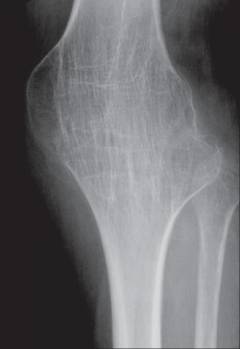

Коленный сустав состоит из трех костей:

- Мыщелки бедренной кости.

- Мыщелки большеберцовой кости.

- Надколенник.

Форма коленного сустава напоминает блок. В нем возможны следующие движения:

- Костный или фиброзный анкилоз – состояние, при котором суставная щель заполняется костной или плотной соединительной тканью, что делает движения невозможными. Диагноз устанавливается с помощью рентгенографии.

- Костный или фиброзный анкилоз – суставная щель зарастает, движения невозможны.